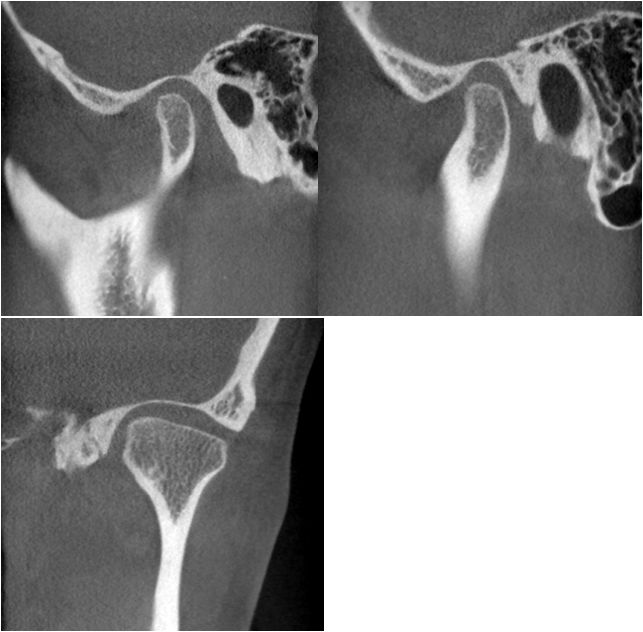

CBCT检查:

从患者双侧颞下颌关节的ct断层影像上看,右侧关节前间隙明显偏小,髁突表面骨皮质较连续但厚度较薄,右侧关节间隙较均匀,个别断面上,髁突表面的骨皮质较粗糙,不明显。左侧颞下颌关节髁突表面骨皮质模糊粗糙,厚度较薄,关节间隙较均匀。临床功能检查上,患者开口度开口型正常,双侧关节张口中期有弹响。

右侧颞下颌关节髁突表面骨皮质连续均匀,关节间隙均匀。左侧颞下颌关节髁突表面骨皮质增厚,个别吸收点消失,关节间隙较均匀。